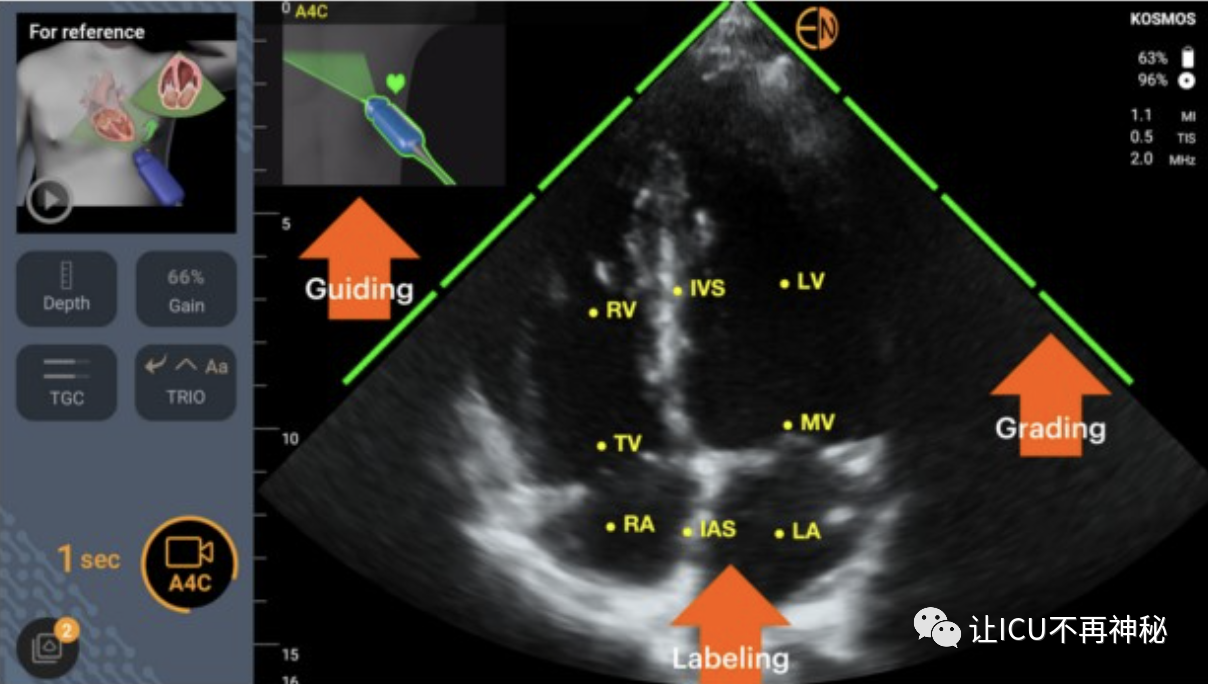

人工智能與治療點(diǎn)超聲心動(dòng)圖已經(jīng)訓(xùn)練了幾種ML算法來識(shí)別心臟圖像,并引導(dǎo)用戶正確握住和定位他們的經(jīng)胸探頭。這樣的算法還能夠?qū)D像質(zhì)量進(jìn)行分級(jí)并標(biāo)記心臟結(jié)構(gòu)。圖1中顯示了一個(gè)示例。一些ML算法可以自動(dòng)進(jìn)行超聲心動(dòng)圖測(cè)量。例如,autoVTI算法可以識(shí)別心臟的5腔心尖視圖,在左心室流出道中自動(dòng)定位脈搏波多普勒卡尺,并在短時(shí)間窗口內(nèi)記錄主動(dòng)脈下速度時(shí)間積分(VTI)(圖1)。最近的一項(xiàng)臨床評(píng)估表明,autoVTI算法可以幫助受訓(xùn)者像超聲心動(dòng)圖專家一樣高效地使用超聲波估計(jì)VTI、腦卒中量(SV~VTI x Pi)和心輸出量。還開發(fā)了幾種ML算法用于左心室射血分?jǐn)?shù)(LVEF)的自動(dòng)估計(jì)。比較研究表明,與專家手動(dòng)測(cè)量相比,它們可以使新手更準(zhǔn)確、更具再現(xiàn)性地測(cè)量LVEF。其他超聲算法已被設(shè)計(jì)為通過下腔靜脈呼吸變化的自動(dòng)量化來預(yù)測(cè)機(jī)械通氣患者的流體反應(yīng)性,或通過肺B線的自動(dòng)量化檢測(cè)肺水腫。總之,ML算法在幫助新手進(jìn)行治療點(diǎn)超聲心動(dòng)圖評(píng)估方面的價(jià)值已在幾項(xiàng)臨床研究中得到證明。然而,鑒于接受過超聲心動(dòng)圖培訓(xùn)的重癥監(jiān)護(hù)醫(yī)生的比例正在急劇增加,人工智能創(chuàng)新是否有必要增加超聲血流動(dòng)力學(xué)評(píng)估的數(shù)量和質(zhì)量仍有待確定。